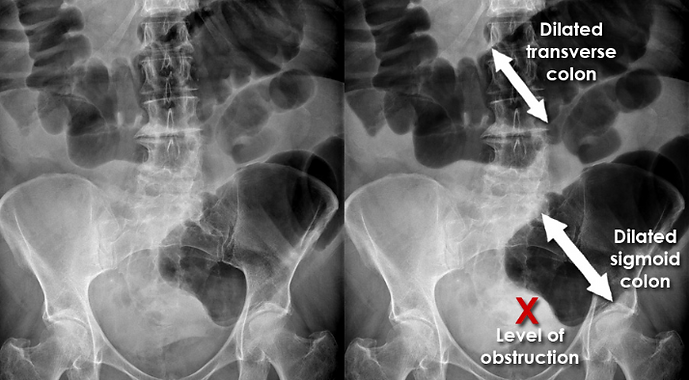

Large bowel: more peripheral, with haustra that don’t cross completely¹.

Large Bowel Obstruction: peripheral colonic dilation; check cecal size (risk of perforation when large). Sigmoid volvulus may present with a coffee-bean sign.1,3,6